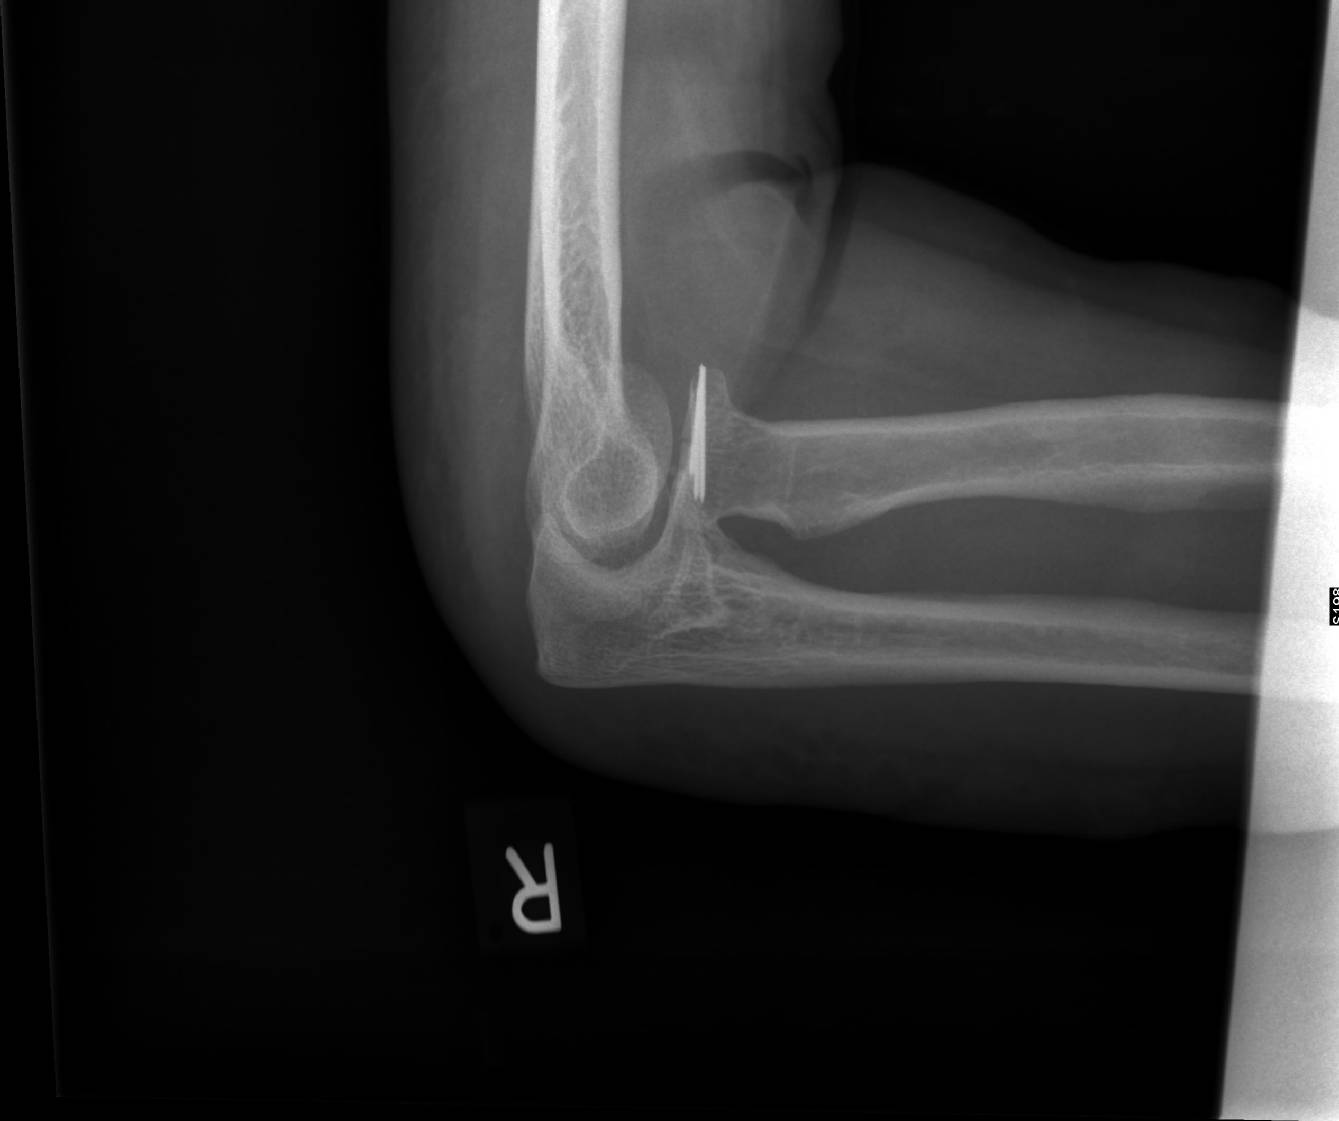

Oberarmbruch

Die Ursache für einen Oberarmbruch (subkapitale Humerus-Fraktur) ist die Krafteinwirkung auf die Schulter oder den ausgestreckten Arm während eines Unfalles oder bei einem Sturz. Die auf Globuli.